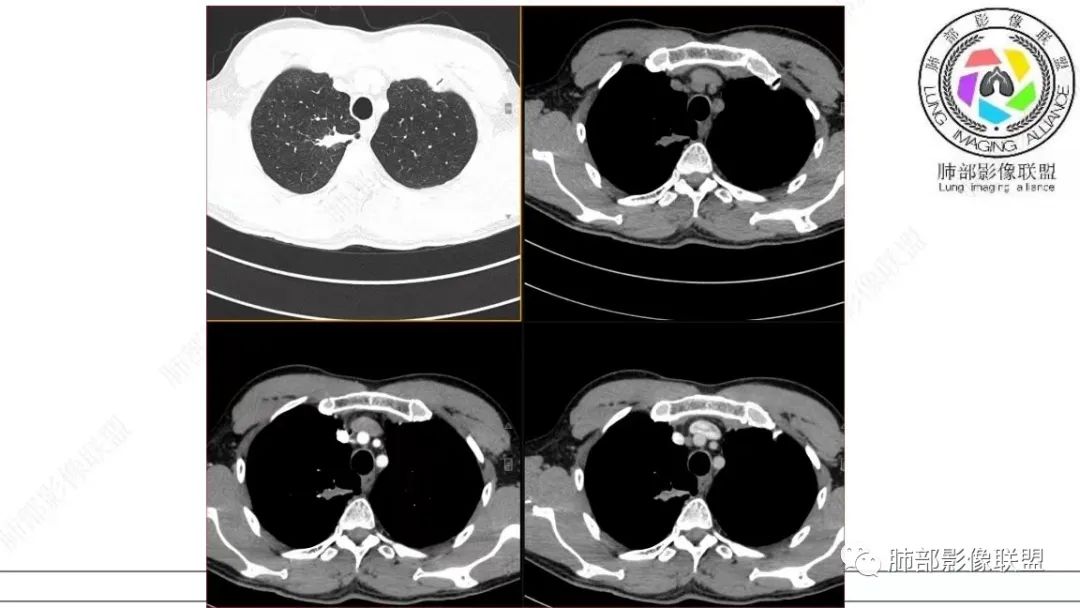

这个病例还可以深挖,图像有点少,我感觉部分层面可疑少许磨玻璃。最难鉴别的是结节型黏液腺癌,特别是细支气管腺瘤的收缩力比较弱的时候。这个病例收缩力太强,结节型黏液腺癌不太好解释。结合病理及影像表现,这个病例最终诊断:倾向于细支气管腺瘤、合并一些非特异性的感染、支气管内粘液栓形成。细支气管腺瘤,疑难。实性的细支气管腺瘤,更疑难。再合并感染,难上加难。不讲理的一个病例。

诸如黏液腺癌这种病变中的黏液,相对于浆液要粘稠一些,虽然合并一部分肿瘤细胞,但是它还是很稀薄的,更容易经气道排出,或沿肺泡孔播散。我感觉很难在细支气管内积聚,形成铸型的这么低的密度。我们看了那么多黏液腺,甚至是大片的,肺炎型。表现更多的是肺泡性病变特点,支气管是衬托出来的含气低密度,或许有轻微扩张。但是没见到过有粘液栓的。

本研究对22处BA的CT影像进行分析,发现以下方面对诊断本病有一定提示意义:①病变部位:本组病例均为周围型病变,多位于下叶,且以胸膜下区为主,与既往研究结果一致。本病细支气管黏膜上皮的起源赋予了其特有的位置分布。②类型:本组GGO14处,实性结节8处。Chang等收集的14处BA中,GGO6处、实性结节8处,与既往研究结果基本一致。此外,部分学者报道呈空洞表现的BA。由此可见,BA的影像表现多样,但主要表现为GGO和实性结节。③大小:本研究显示BA普遍较小,最大径约(0.9±0.7)cm,95%的病变不超过2.0cm。王蓓等、高何等分别纳入8例、15例BA,病灶平均最大径均为1.0cm,与本研究结果一致。④形态:本组BA无论表现为GGO还是实性结节,其形态不规则且边缘毛糙,仅少部分体积较小的BA可呈类圆形或椭圆形,与Kamata等的研究结果相似,推测BA的形态学改变与肿瘤无包膜有关。⑤伴发征象:本研究中BA多伴有中央或外周空泡征、细支气管充气征及血管征,其中以中央空泡征最具特征。刘芳兵等报道2例表现为GGO的BA均伴空泡征;苏雷等报道11例BA中,伴有空泡征8例、血管征10例。可见空泡征和血管征对诊断本病具有重要意义。上述征象与镜下瘤内、瘤周常见细支气管及伴行的厚壁血管有关。此外,胸膜牵拉征、分叶征及毛刺征罕见。⑥强化方式:实性结节表现的BA增强扫描呈延迟性显著强化,部分病灶动脉期可见血管造影征,血管走行自然,未见破坏。血管造影征与镜下病变常见细支气管动脉束穿行相符,此征象也反映了肿瘤位于细支气管周围的定位。⑦随访中病灶保持稳定或缓慢增长。此段内容及病例图片摘自并感谢,黄勇教授、王越老师-细支气管腺瘤的CT表现,发表于中国医学影像杂志。